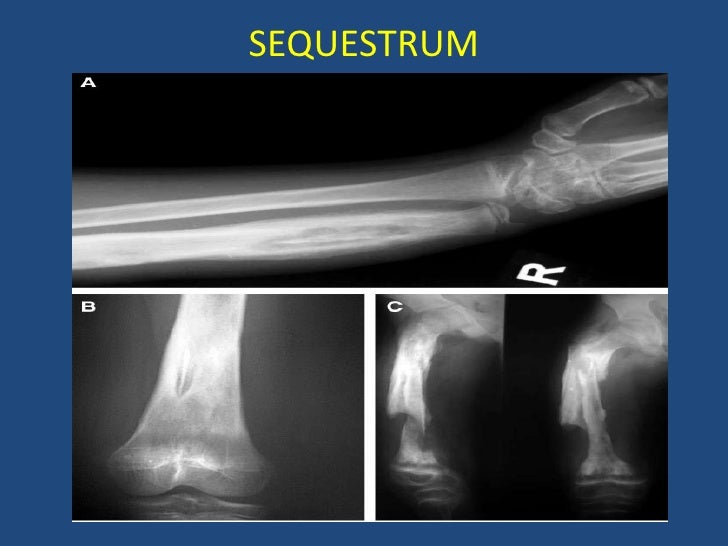

Chronic Osteomyelitis In Children

Chronic Osteomyelitis In Children Oral Zyvox For Osteomyelitis In no published studies was iv superior in efficacy. The pharmacokinetic profile of oral linezolid makes it an attractive alternative for the treatment of osteomyelitis. In summary, oral options for the treatment of chronic osteomyelitis based on pharmacokinetic considerations include fluoroquinolones, tmp. We investigated whether oral antibiotic therapy is noninferior to intravenous antibiotic therapy for this. With the advances in. Oral Zyvox For Osteomyelitis.